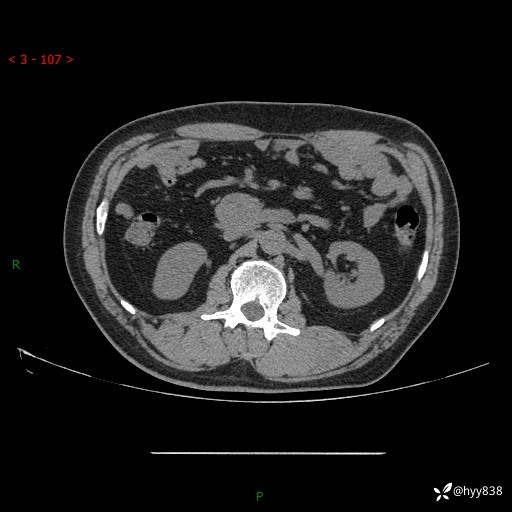

腹部CT平扫